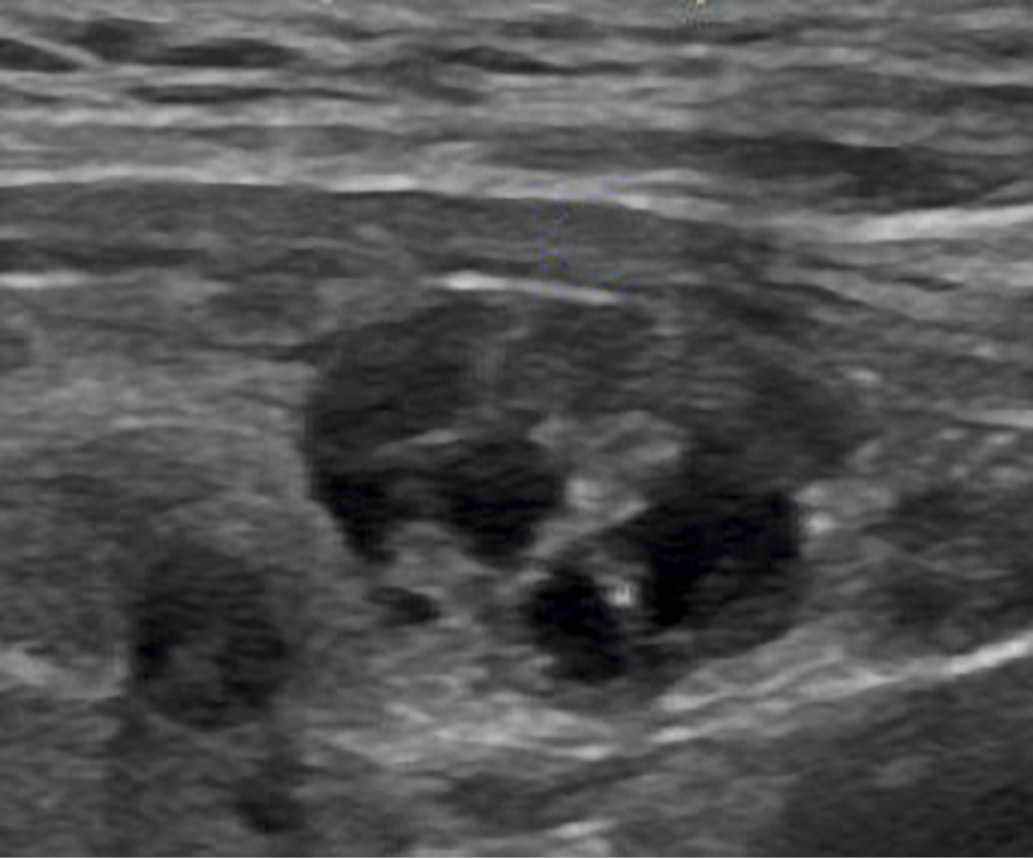

1. Рис. 1. Анэхогенное образование ЩЖ с перегородками (EU-TIRADS 2). | |